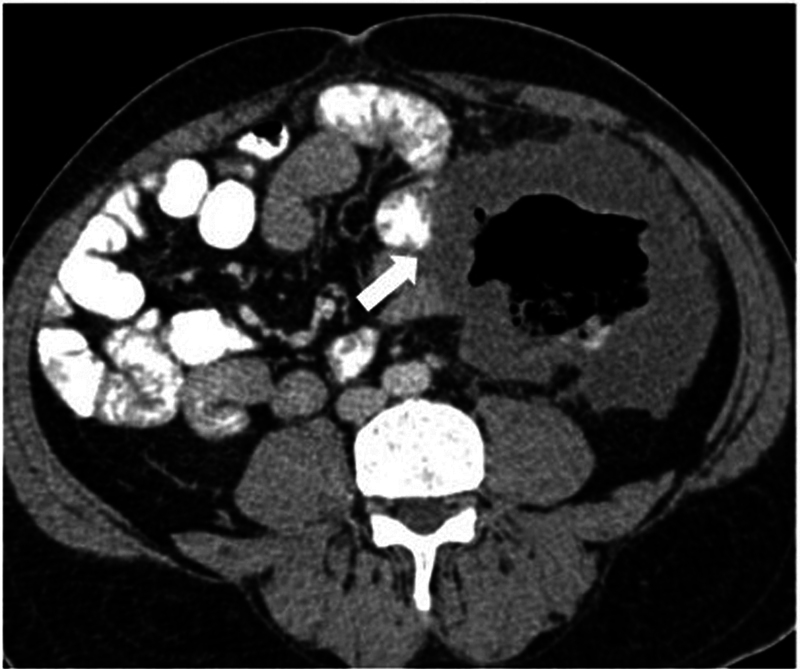

本文综述了计算机断层扫描(CT)、CT结肠镜检查(CTC)和磁共振成像(MRI)在结直肠癌的诊断、分期、疗效评估和随访中的作用。对于CT扫描,需要事先进行肠道准备。这是通过使用口服或直肠造影剂来增强结肠成像。像空气或二氧化碳之类的阴性对比有助于通过扩张结肠来检测息肉和肿块。虚拟结肠镜检查为息肉和癌症的检测提供了一种低辐射的选择。动脉和静脉相CT图像的静脉造影剂管理对于已知结肠癌病例的完全分期和残留/复发疾病的评估也很重要。对于MRI来说,多平面的高分辨率t2加权图像很重要,弥散加权成像(DWI)序列对重新定位很重要。一般不推荐静脉造影剂。对比增强CT和MRI用于淋巴结和远处转移分期,特别注意盆腔侧壁淋巴结。如果发现不明确或怀疑复发,应考虑进行正电子发射断层扫描(PET) CT进一步评估。

The present review highlights the role of computed tomography (CT), CT colonography (CTC), and magnetic resonance imaging (MRI) in the diagnosis, staging, response evaluation, and follow-up of colorectal cancer. For a CT scan, prior bowel preparation is required. This is done to enhance imaging of the colon with the use of oral or rectal contrast agents. Negative contrast like air or carbon dioxide are helpful in detecting polyps and masses by distending the colon. Virtual colonoscopy offers a lower-radiation alternative for polyp and cancer detection. Intravenous contrast administration with arterial and venous phase CT images is also important in complete staging of a known case of colon cancer and for evaluation of residual/recurrent disease. With respect to MRI, high-resolution T2-weighted images in multiple planes are important, with diffusion-weighted imaging (DWI) sequences being important for restaging. Intravenous contrast is not generally recommended. Contrast-enhanced CT and MRI are used for nodal and distant metastasis staging, with special attention to the pelvic side wall nodes. Positron emission tomography (PET) CT is to be considered for further evaluation if the findings are unclear and recurrence is suspected.